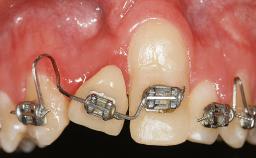

Periodontal Plastic Surgery and Prosthetic Procedures to Treat Peri-Implant Soft-Tissue Dehiscences

A 30-year-old woman was referred by her general dentist for evaluation of an esthetic complication related to previous implant treatment for congenitally missing maxillary lateral incisors. The patient’s chief complaint was the inadequate esthetic appearance of her smile. The case demonstrates the use of a combined approach to achieve optimal results. Two different flap designs - a tunnel technique and a coronally advanced flap - are employed based on the surgical objectives for the affected site.